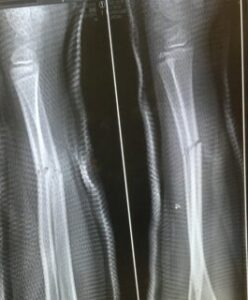

サッカー教室でゲームをしているときに子供が転んで手を痛めました。

痛みの場所が手首からずれていたのと、痛みも強かったので、すぐに病院に連れて行きました。

すると、案の定、骨折。

去年秋に指を骨折し、今年1月には左腕を骨折し救急車で運ばれ、手術をするかしないかの大けが。

先月ようやく最後の通院が終わったと思っていたら、今度は右手首。